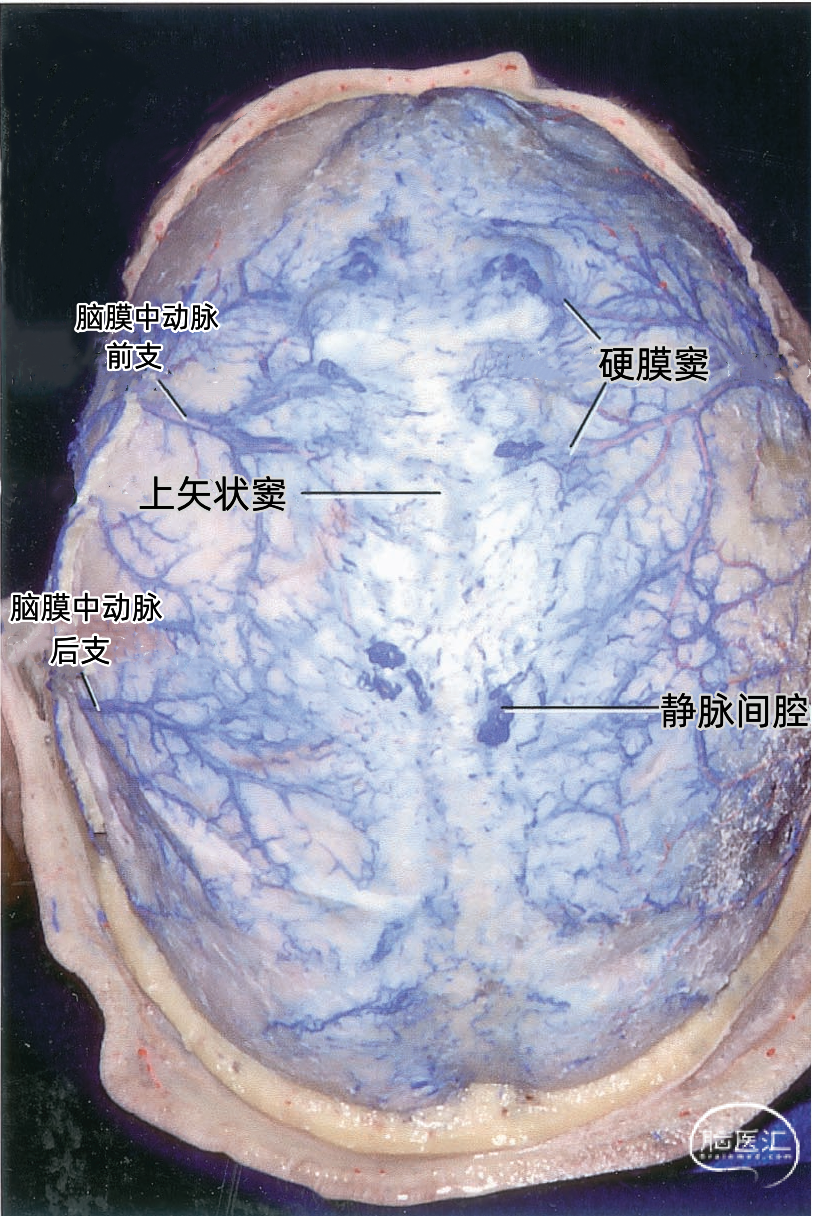

上矢状窦(superior sagittal sinus SSS)位于中线,引流额叶下面的前部和额叶、顶叶、枕叶外侧面及内侧面的上部。 上矢状窦的冠状切面呈三角形,左右两个侧角与覆盖半球凸面的硬脑膜相连接,下角与大脑镰相连。上矢状窦的三角形管腔前部较细,向后逐渐扩大。 上矢状窦两侧壁有的地方向外膨隆扩张,形成外侧陷窝。外侧陷窝常有大脑皮层静脉汇入,还有蛛网膜颗粒突入其中。上矢状窦的下角和外侧陷窝之间常有许多横行的纤维相连。在上矢状窦后部的窦壁内有一海绵状间隙系统,在窦壁内皮与硬脑膜之间,形成海绵状间隙,参与调节脑血流量。

外侧陷窝通常很复杂,几乎呈丛状,很少以简单的中空形式存在。矢状窦、横窦和直窦旁丛状分布的小静脉以及“海绵”静脉组织的脊往往与上矢状窦和横窦的管腔相交通。上矢状窦内也有一些纤维束形成隔将其管腔分为上、下两个通道。

上矢状窦在前方可能通过盲孔与鼻腔的静脉相交通。上矢状窦在枕内粗隆处通过窦汇静脉丛复合体引流入横窦,上矢状窦可均等引流入左右横窦,也可以一侧横窦为主或完全引流入一侧,但一般是右侧横窦接受主要的回流。

▼2.静脉腔隙

静脉腔隙(Venous lacunae),也称为静脉湖、静脉间腔、静脉间隙,来自硬脑膜的引流静脉在上矢状窦附近扩大形成静脉腔隙,它位于两层硬脑膜之间(下图)。 静脉腔隙主要接受硬脑膜内硬脑膜静脉的回流,也引流板障静脉的血液。 静脉腔隙内壁有蛛网膜颗粒(上图),进入上矢状窦的皮层静脉(上图)往往在静脉腔隙下方走行,直接汇入矢状窦,而不是直接进入静脉腔隙。大部分途经静脉腔隙下方的静脉与静脉腔隙分别开口入窦,但有些静脉与静脉腔隙有共同的入窦开口,极少数的静脉直接引流入静脉腔隙。 也有桥静脉(上图)先在窦旁潜行进入硬膜再汇入窦,硬膜内潜行使空腔扩大形成硬膜窦。静脉腔隙和硬膜窦都与矢状窦相通。 额叶后部和顶部的静脉腔隙最大和最恒定,枕部和额叶前部的静脉腔隙较小(上图)。 通常每侧都有2或3个这样的静脉腔隙,额部一个小静脉腔隙,顶部一个大的静脉腔隙,枕部一个大小介于前两者之间的静脉腔隙。 在年龄大的个体,这些腔隙趋向于融合,以致于每侧形成一个纵长的腔隙(下图)。 下图示切除大的静脉腔隙,显露下方进入上矢状窦的静脉。左侧中央静脉在中央沟上端注入上矢状窦。右侧中央静脉向前越过中央前回加入上矢状窦。

下图示切除静脉腔隙,显示上矢状窦右侧面。可见静脉在静脉腔隙下方进入上矢状窦。额内侧静脉、额外侧静脉以及顶内侧静脉、顶外侧静脉经常在入窦前汇合成共干,然后进入上矢状窦。

▼3.脑膜静脉

引流硬膜血液的小静脉通道称为脑膜静脉。它们其实是小静脉窦。脑膜静脉多数与脑膜动脉伴行,一般是每一条动脉有一条伴行静脉,但脑膜中动脉有两条伴行静脉。与脑膜动脉伴行的脑膜静脉走行在动脉与骨板之间,实际上伴行的动脉嵌入静脉内,看起来是平行的静脉管腔位于动脉的两侧。 有的脑膜静脉可能在颅骨内板的浅沟内走行,有板障内和硬膜内两个行程,使得颅骨骨折时尤其易于被撕裂。 硬脑膜的动脉和静脉之间存在着丰富的血管吻合。动脉与静脉常常并列行进,而且存在着50~90μm的动、静脉交通,以在静脉窦附近多见,在临床上容易形成硬脑膜动-静脉瘘。 脑膜静脉末段管腔扩大不明显,主要汇入附近的硬脑膜窦,特别是上矢状窦两侧的外侧陷窝。在大脑的上缘,进入静脉腔隙或上矢状窦。在大脑的下缘,脑膜静脉进入颅底的大静脉窦。 脑膜中静脉属支通过上矢状窦的静脉腔隙与上矢状窦相交通。这些属支在下方彼此汇聚并融合成额干、顶干。脑膜中静脉额干伴行于脑膜中动脉前支经卵圆孔达翼静脉丛或者进入蝶顶窦、海绵窦或蝶骨导静脉;脑膜中静脉顶干伴行于脑膜中动脉后支可经棘孔与翼静脉丛交通。

下图示覆盖在大脑半球表面的硬膜,包含有沿脑膜中动脉分支分布的小硬膜窦的丛。最大的硬膜窦沿着脑膜中动脉前、后分支分布,向上进入上矢状窦或其附近的静脉腔隙。